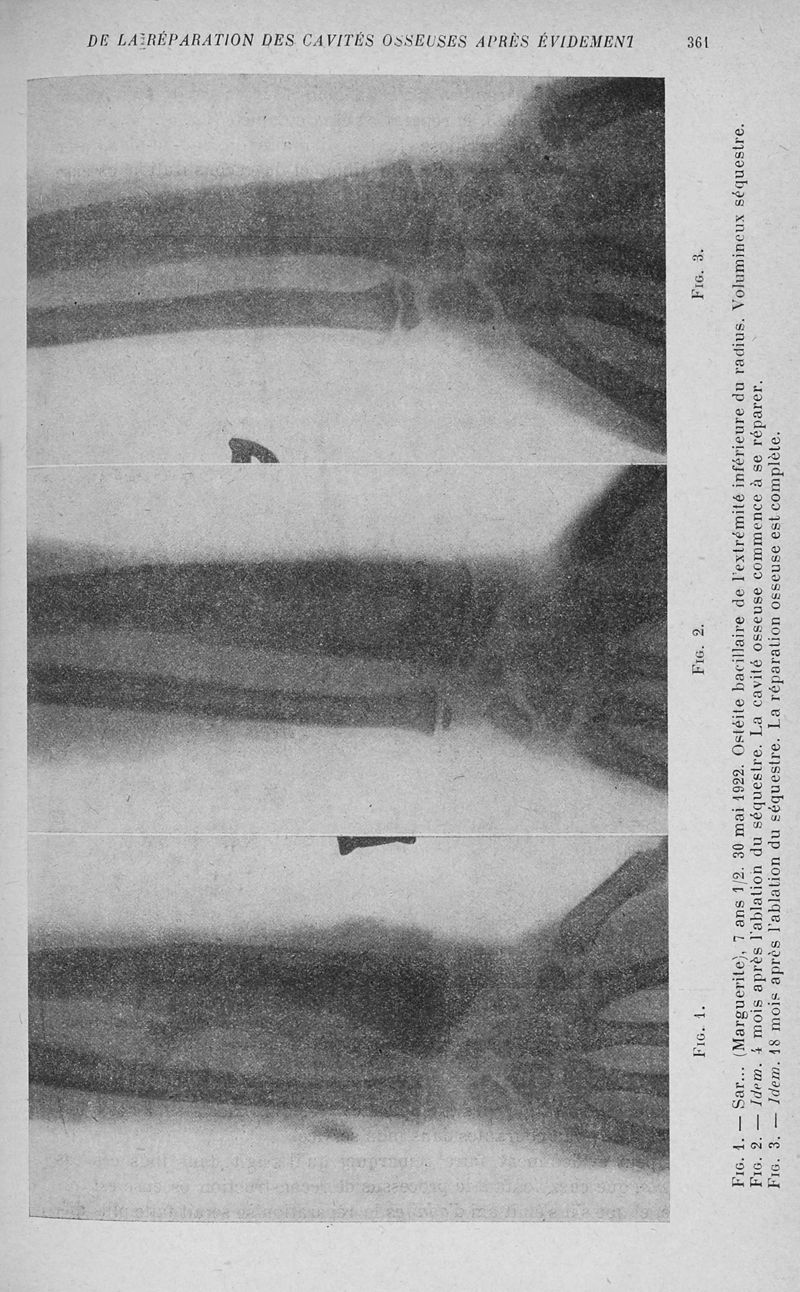

Bulletins et mémoires de la société nationale de chirurgie

Tome LII, 1926. - Paris : Masson, 1926.